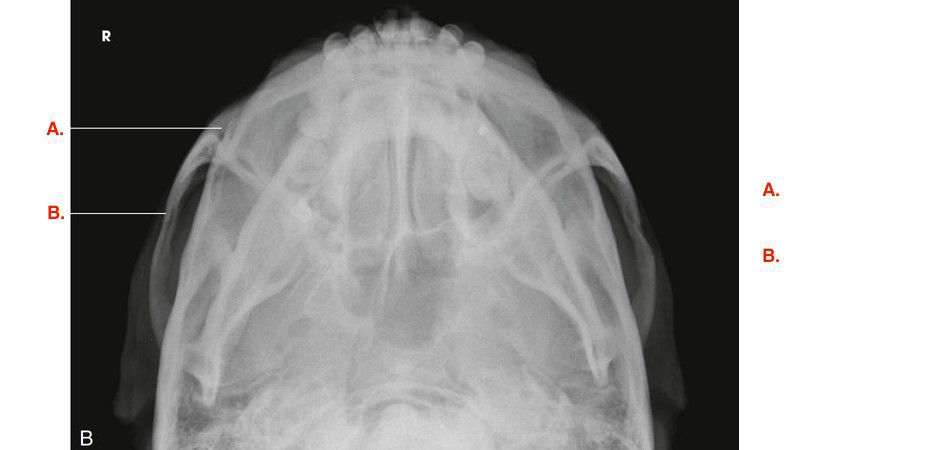

Question 2

Question

Label the image

Image:

5546e6ef-233f-486d-8766-2e51aa5cb5f8 (image/jpeg)

Answer

orbit

zygomatic arch

maxillary sinus

maxilla

petrous ridge

mandibular angle